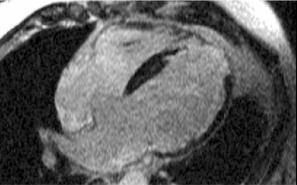

- Resonancia magnética cardíaca (RMC)

Permite realizar el diagnóstico diferencial entre la miocardiopatía dilatada y la isquémica.

Miocardiopatía dilatada

No existe captación de gadolinio.